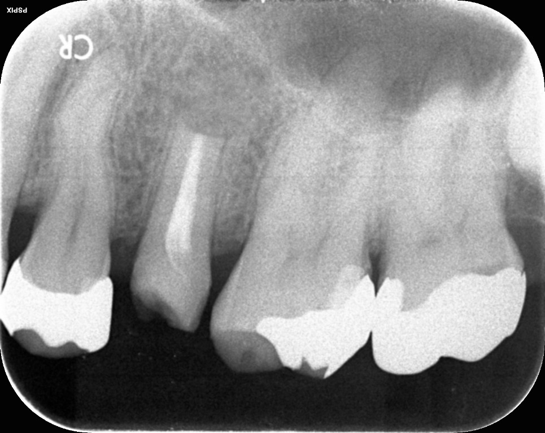

次の画像は、同じ患部をCTとレントゲンで撮影した画像です。

• 比較

「左」の写真がCTで、「右」の画像がレントゲンで撮影したものです。

赤丸で囲んだところには、黒い影が見えます。ここには炎症が起こっているのですが、右の写真には影がありません。つまり、2次元のレントゲンだけで診断した場合、問題のある部分は治療しない選択をするため、最終的には抜歯の運命をたどるケースです。